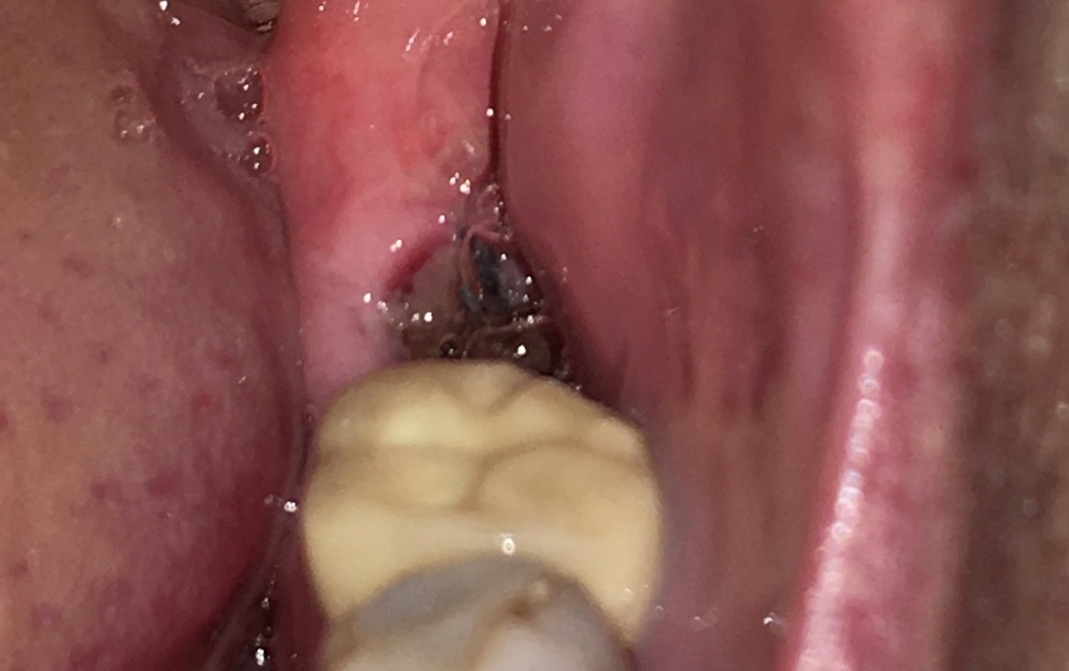

The hole in my gum where the tooth used to be.So let’s get down to business - what is the difference between dry socket vs normal pain?

First, with a dry socket you will probably have a bad taste or a bad smell in your mouth. Next, you will start to get pain in the extraction socket 4 to 5 days AFTER the extraction.You will NOT have any swelling in the area at all.

The pain IS caused by the tooth extraction socket being EMPTY, without any blood clot or healing in there. The bone inside the socket is exposed. You have an empty tooth socket.

IT IS THE EXPOSED BONE THAT CAUSES THE PAIN.

BUT IF THE BLOOD CLOT GETS WASHED OUT OF THE SOCKET before it has a chance to stabilize, then you are left with an empty socket. WITH EXPOSED BONE. You have a “dry” socket.